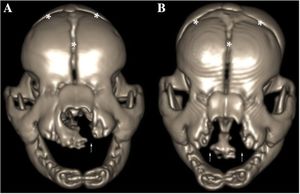

Computed Tomographic Evaluation of Cleft Palate in One-day-old Puppies

Publication: BMC Vet Res. 2018 Oct 20;14(1):316. PMID: 30342508 | PDF Authors: Pankowski F, Paśko S, Max A, Szal B, Dzierzęcka M, Gruszczyńska J, Szaro P, Gołębiowski M, Bartyzel BJ. Institution: Department of Morphological Sciences, Faculty of Veterinary Medicine, Warsaw University of Life Sciences - SGGW, Warsaw, Poland. Abstract: BACKGROUND: Cleft palate is a birth defect characterized by a lack of fusion between structures forming the palate. Causes include a multitude of factors, both genetic and environmental. Computed tomography (CT) is widely used to evaluate morphological features and diagnose head disorders in adult dogs. However, there is less data about its use in neonatal dogs. The purpose of this study was to perform CT evaluation of palatal defects in one-day-old puppies and to present a novel approach of 3D modeling in terms of cleft palate assessment. RESULTS: Macroscopic and CT examinations were performed in 23 stillborn or euthanized purebred newborn puppies. On the basis of CT data, a 3D model was prepared and the cleft surface area was then calculated. A multi-stage approach, which utilised software such as 3D Slicer and Blender, was applied. Palatal defects were found in ten dogs, of which five had cleft palate, three had bilateral cleft lip and palate, one had a unilateral cleft lip and palate and one had a unilateral cleft lip. The surface area of the clefts ranged from 31 to 213 mm2, which made up respectfully 11 to 63% of the total surface area of the palate. No abnormalities were found in thirteen dogs and they made up the control group. CONCLUSIONS: Computed tomography and 3D modeling were very effective in evaluation of palatal disorders in newborn dogs. 3D models adapted to the natural curvature of the palate were created and more precise data was obtained. Morphological characteristics, CT findings and advanced image analysis of cleft palate in neonates obtained from these models increase the knowledge about this malformation in dogs. |